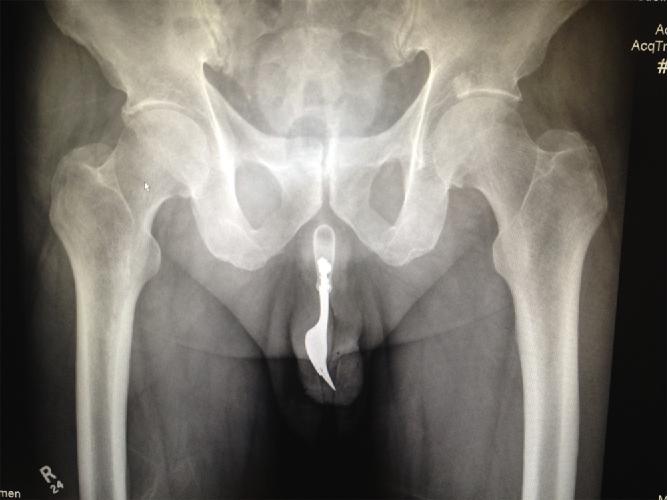

叉子丨参考文献7

[7]K. Naidu, A. Chung, M. Mulcahy. An unusual urethral foreign body. International Journal of Surgery Case Reports. Volume 4, Issue 11, 2013, Pages 1052-1054